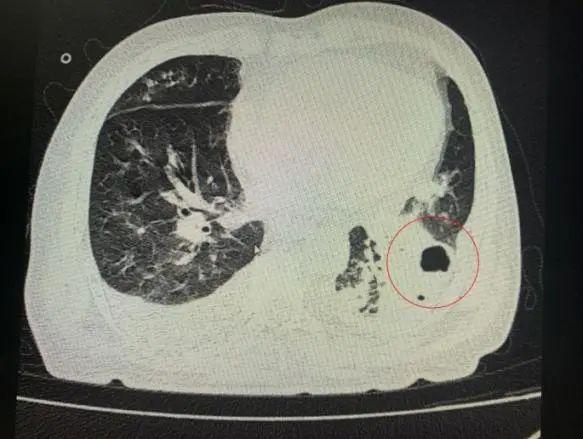

番禺院区呼吸内科何梦璋主任接诊后,对钟叔进行详细检查。此时,钟叔的病情已经十分危急,由于不能自主呼吸,他带上了无创呼吸机辅助呼吸治疗。看到钟叔胸片时,医护人员头皮也一阵发麻,胸部CT可见双肺多发的炎症浸润、双肺多发空洞。通俗来说,钟叔的肺部已经被病原体蚕食,啃出无数个大小各异的洞!可怕的是,这种病变对肺功能的破坏是永久性、不可恢复的。根据钟叔病史以及胸部CT结果,最终诊断为“吸入性肺脓肿”

钟叔的肺部被病原体蚕食,啃出无数个大小各异的洞。

经过2周多的治疗,钟叔病情有所改善,按照家属的要求转回当地医院继续治疗。钟叔还需要进行半年以上的后续治疗,包括持续的抗菌药物治疗,以及定期胸部CT复查,动态监测肺部病灶情况。据医生表示,由于病原体已经对钟叔的肺部造成不可逆的破坏,即使炎症消失,肺功能也并不能完全恢复,最常见的表现是活动耐力下降。